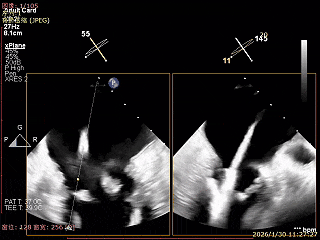

Bicomm切面看2区脱垂

上Color,可见反流主要来自于3区

X-Plane切面切1区未见明显异常

1区上Color,未见反流来源

X-Plane切面切2区可见前叶Flail

2区上Color,可见反流来源

X-Plane切面切3区可见前叶脱垂

3区上Color,可见反流来源

3D Enface 2区及3区前叶脱向左房

3D Enface 可见反流由2区3区从前后冲出